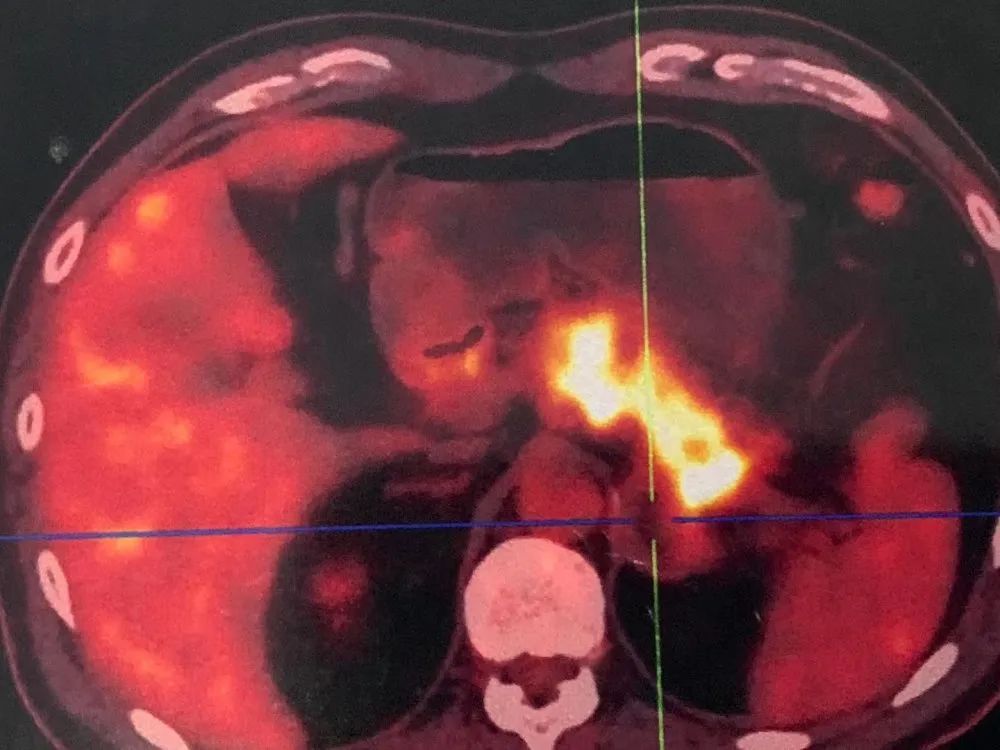

5月7日PET-CT檢查發(fā)現(xiàn):胰腺體尾部增粗伴周圍滲出性改變,F(xiàn)DG高代謝,惡性腫瘤可能性大;左側(cè)腎上腺術(shù)后,左側(cè)腎上腺區(qū)不均質(zhì)密度占位。為更進一步了解病情,隨后許先生在5月13日做了腹部、盆腔增強CT:胰腺體尾部惡性腫瘤伴左腎上腺受累,脾靜脈、腸系膜上靜脈及門脈主干受累可能性大;并在上海某醫(yī)院接受胰腺腫瘤穿刺活檢,病理顯示:胰腺低分化腺癌。